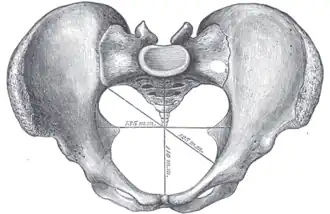

A distinction is made between the lesser or true pelvis inferior to the terminal line, and the greater or false pelvis above it. The pelvic inlet or superior pelvic aperture, which leads into the lesser pelvis, is bordered by the promontory, the arcuate line of ilium, the iliopubic eminence, the pecten of the pubis, and the upper part of the pubic symphysis. The pelvic outlet or inferior pelvic aperture is the region between the subpubic angle or pubic arch, the ischial tuberosities and the coccyx. [3]

Alternatively, the pelvis is divided into three planes: the inlet, midplane, and outlet.[4]

Diameters of pelvic inlet